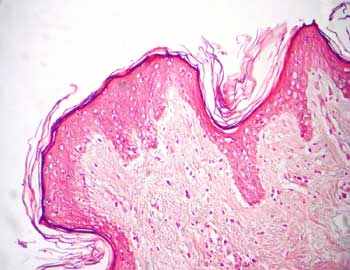

Visión general: presentamos un fragmento de piel fina para estudiar tanto el epitelio o epidermis como el conjuntivo laxo común que aparece justo por debajo de la capa epitelial constituyendo la dermis papilar y el conjuntivo fibroso denso no modelado e irregular, que conforma la dermis reticular, por debajo. En la profundidad encontraremos la hipodermis con abundante tejido adiposo y gruesas estructuras vasculares.

Visión específica: el tejido epitelial que cubre la superficie libre de este preparado, la epidermis, es un epitelio plano pluriestratificado queratinizado. La capa mas profunda esta constituida por una fila de células cúbicas, el estrato basal, por encima un número variable de capas de células poliédricas que progresivamente se van aplanando, el estrato espinoso, y ya en superficie, las células mas diferenciadas en su proceso madurativo las del estrato granuloso y del estrato córneo. En este caso es una piel fina por lo que la capa superficial de células anucleadas o escamas córneas no es muy ámplia. Se evidencia a mayores aumentos la diversa arquitectura de las tres regiones del conjuntivo o dermis. En la dermis papilar fibras mas finas y fundamentalmente orientadas perpendicularmente hacia la lámina epitelial y entre las que se observan numerosas células y capilares. Distinguimos el carácter fasciculado de los gruesos haces de las fibras de colágena, de la dermis reticular, separados por material no teñido que corresponde con la sustancia fundamental, y en donde se observan débilmente teñidas aisladas células y vasos. En profundidad podemos encontrar también glándulas sudoríparas, tanto porción secretora como excretora. En la porción más profunda podremos visualizar la estructuración de la hipodermis, con el tejido adiposo y las grandes estructuras vasculares que la conforman.